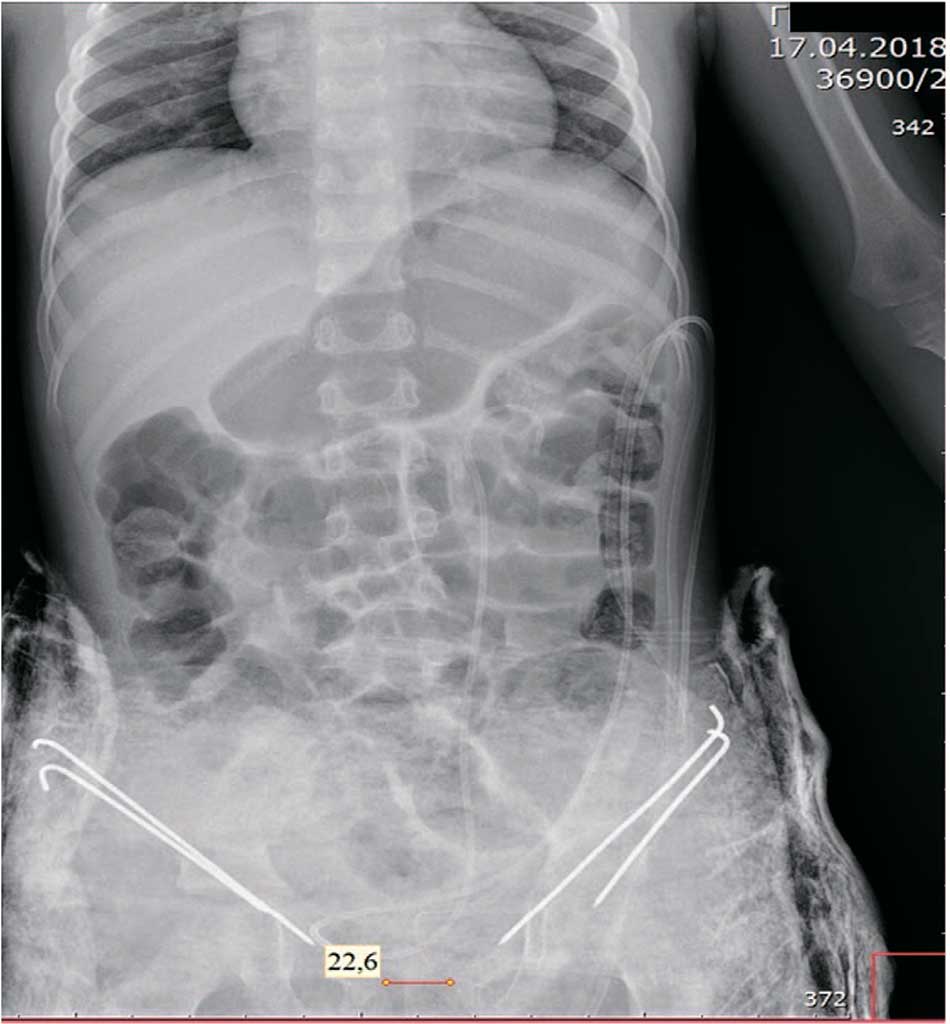

Выполнена двусторонняя подвздошная надацетабулярная остеотомия. На лонные кости таза наложены внутрикостные швы «викрил» 2, мочевой пузырь погружен в полость таза, и над ним максимально сведены к центру лонные кости узловыми швами. Остаточный диастаз костей лона составил около 2 см. В области остеотомии костные отломки фиксированы двумя спицами Киршнера с каждой стороны (рис. 4).

Рис. 4. Пациент Г. Обзорная R-грамма костей таза на 1-е сутки после операции

Fig. 4. Patient G. General X-ray of the pelvic bones on the 1st day after surgery